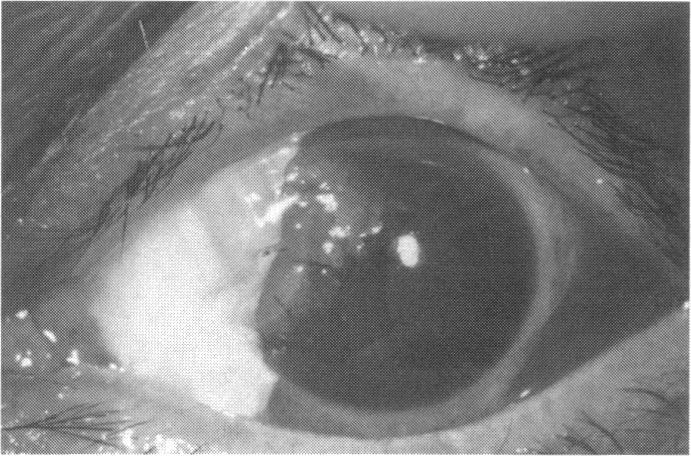

Human Subjects. Of the 19 human subjects included, 18 (20 procedures) underwent in vitro cultured corneal epithelial cell transplants using various carriers for the epithelial cells to determine the most efficacious approach. Sixteen patients (18 procedures on 17 eyes) received autologous transplants, and 2 patients (1 procedure each) received allogeneic sibling grafts. The presumed corneal epithelial stem cells from 1 patient did not grow in vitro. The carriers for the expanded corneal epithelial cells included corneal stroma, type 1 collagen (Vitrogen), soft contact lenses, collagen shields, and amniotic membrane for the autologous grafts and only amniotic membrane for the allogeneic sibling grafts. Histologic confirmation was reviewed on selected donor grafts. Amniotic membrane as carrier. Further studies were made to determine whether amniotic membrane might be the best carrier for the expanding corneal epithelial cells. Seventeen different combinations of tryspinization, sonication, scraping, and washing were studied to find the simplest, most effective method for removing the amniotic epithelium while still preserving the histologic appearance of the basement membrane of the amnion. Presumed corneal epithelial stem cells were harvested and expanded in vitro and applied to the amniotic membrane to create a composite graft. Thus, the composite graft consisted of the amniotic membrane from which the original epithelium had been removed without significant histologic damage to the basement membrane, and the expanded corneal epithelial stem cells, which had been applied to and had successfully adhered to the denuded amniotic membrane. Animal model. Twelve rabbits had the ocular surface of 1 eye damaged in a standard manner with direct removal of the presumed limbal stem cells, corneal epithelium, and related epithelium, followed by the application of n-heptanol for 60 seconds. After 6 weeks, all damaged eyes were epithelialized and vascularized. Two such treated eyes were harvested without further treatment, to be used for histologic study as damaged controls. The remaining 10 rabbits received composite grafts (consisting of amniotic membrane with expanded allogeneic rabbit corneal epithelial cell transplants) applied to the ocular surface in a standard manner followed by the application of a contact lens. At 16 days following transplantation, 5 of the rabbits were sacrificed and the corneal rims were removed for histologic study. At 28 days, the remaining rabbits were sacrificed and the previously damaged eyes were harvested for histologic and immunohistochemical study.

RESULTS

Human subjects. Of the 19 total patients admitted to the study, the presumed corneal epithelial stem cells of 1 patient did not grow in vitro. Of the remaining 18 patients (20 procedures, 19 eyes), 3 patients had unsuccessful results (3 autologous procedures), 1 patient had a partially successful procedure (allogeneic procedure), and 1 patient had a procedure with an undetermined result at present (allogeneic procedure). One unsuccessful patient had entropion/trichiasis and mechanically removed the graft and eventually went into phthisis. The other 2 unsuccessful patients suffered presumed loss of autologous donor epithelium and recurrence of the ocular surface disease (pterygium). The partially successful patient receiving an allogeneic transplant had infectious keratitis delay of his re-epithelialization; he has only minimal visual improvement but has re-epithelialized. The patient receiving the second allogeneic graft lost his donor epithelium at day 4. Additional donor epithelium was reapplied, but the result is undetermined at present. Amniotic membrane as carrier. The in vitro preparation of the amniotic membrane with corneal epithelial stem cell graft overlay was successful. Histology documented removal of the amniotic epithelium and reapplication of corneal epithelial cells. Animal model. The 2 rabbits that had no reparative surgery following standard ocular surface injury had histology and immunopathology consistent with incomplete corneal epithelial stem cell failure with vascularization and scarring of the ocular surface. Light microscopy and immunohistologic staining with AE5 confirmed the conjunctival phenotype of the ocular surface repair but also documented the incomplete model. The allogeneic stern cell transplants had varying results. One rabbit had a suppurative infection and lost the graft. Reparative surgery failed in 2 of the rabbits, failed partially in 3 of the rabbits, was partially successful in 3 others, and was successful in 1 rabbit at 28 days. Histologic and immunopathologic study documented successful growth of corneal epithelium onto the recipient surface.

人类受试者。纳入的19名人类受试者中,18名(20例手术)使用上皮细胞的各种载体进行了体外培养角膜上皮细胞移植,以确定最有效的方法。16例患者(17只眼的18例手术)接受了自体移植,2例患者(各1例手术)接受了异体同胞移植。1例患者的假定角膜上皮干细胞在体外未生长。扩增角膜上皮细胞的载体包括角膜基质、1型胶原蛋白(Vitrogen)、软性隐形眼镜、胶原盾和羊膜用于自体移植,而异体同胞移植仅使用羊膜。对选定的供体移植物进行了组织学确认。羊膜作为载体。进一步研究以确定羊膜是否可能是扩增角膜上皮细胞的最佳载体。研究了17种不同的胰蛋白酶消化、超声处理、刮除和冲洗组合,以找到去除羊膜上皮同时仍保留羊膜基底膜组织学外观的最简单、最有效的方法。采集假定的角膜上皮干细胞并在体外扩增,然后应用于羊膜以制备复合移植物。因此,复合移植物由已去除原始上皮且基底膜无明显组织学损伤的羊膜以及已应用并成功粘附于裸露羊膜的扩增角膜上皮干细胞组成。动物模型。12只兔子的1只眼的眼表以标准方式受损,直接去除假定的角膜缘干细胞、角膜上皮和相关上皮,然后应用正庚醇60秒。6周后,所有受损眼均上皮化且血管化。2只经如此处理的眼未进一步治疗即被采集,用作组织学研究的受损对照。其余10只兔子接受以标准方式应用于眼表的复合移植物(由带有扩增异体兔角膜上皮细胞移植的羊膜组成),随后应用隐形眼镜。移植后16天,处死5只兔子,取出角膜缘进行组织学研究。28天时,处死其余兔子,取出先前受损的眼进行组织学和免疫组织化学研究。

结果

人类受试者。纳入研究的19例患者中,1例患者的假定角膜上皮干细胞在体外未生长。其余18例患者(20例手术,19只眼)中,3例患者手术结果不佳(3例自体手术),1例患者手术部分成功(异体手术),1例患者目前手术结果未确定(异体手术)。1例手术失败的患者患有睑内翻/倒睫,机械性移除了移植物,最终眼球萎缩。另外2例手术失败的患者假定自体供体上皮丢失且眼表疾病(翼状胬肉)复发。接受异体移植的部分成功患者发生感染性角膜炎,上皮化延迟;他的视力仅略有改善,但已重新上皮化。接受第二次异体移植的患者在第4天失去了供体上皮。重新应用了额外的供体上皮,但目前结果未确定。羊膜作为载体。羊膜与角膜上皮干细胞移植物覆盖物的体外制备成功。组织学证实羊膜上皮已去除且角膜上皮细胞已重新应用。动物模型。2只在标准眼表损伤后未进行修复手术的兔子的组织学和免疫病理学结果与角膜上皮干细胞不完全衰竭一致,伴有眼表血管化和瘢痕形成。光学显微镜检查和用AE5进行的免疫组织化学染色证实了眼表修复的结膜表型,但也记录了不完全模型。异体干细胞移植结果各异。1只兔子发生化脓性感染,移植物丢失。2只兔子的修复手术失败,3只兔子部分失败,另外3只部分成功,1只兔子在28天时成功。组织学和免疫病理学研究记录了角膜上皮在受体表面的成功生长。